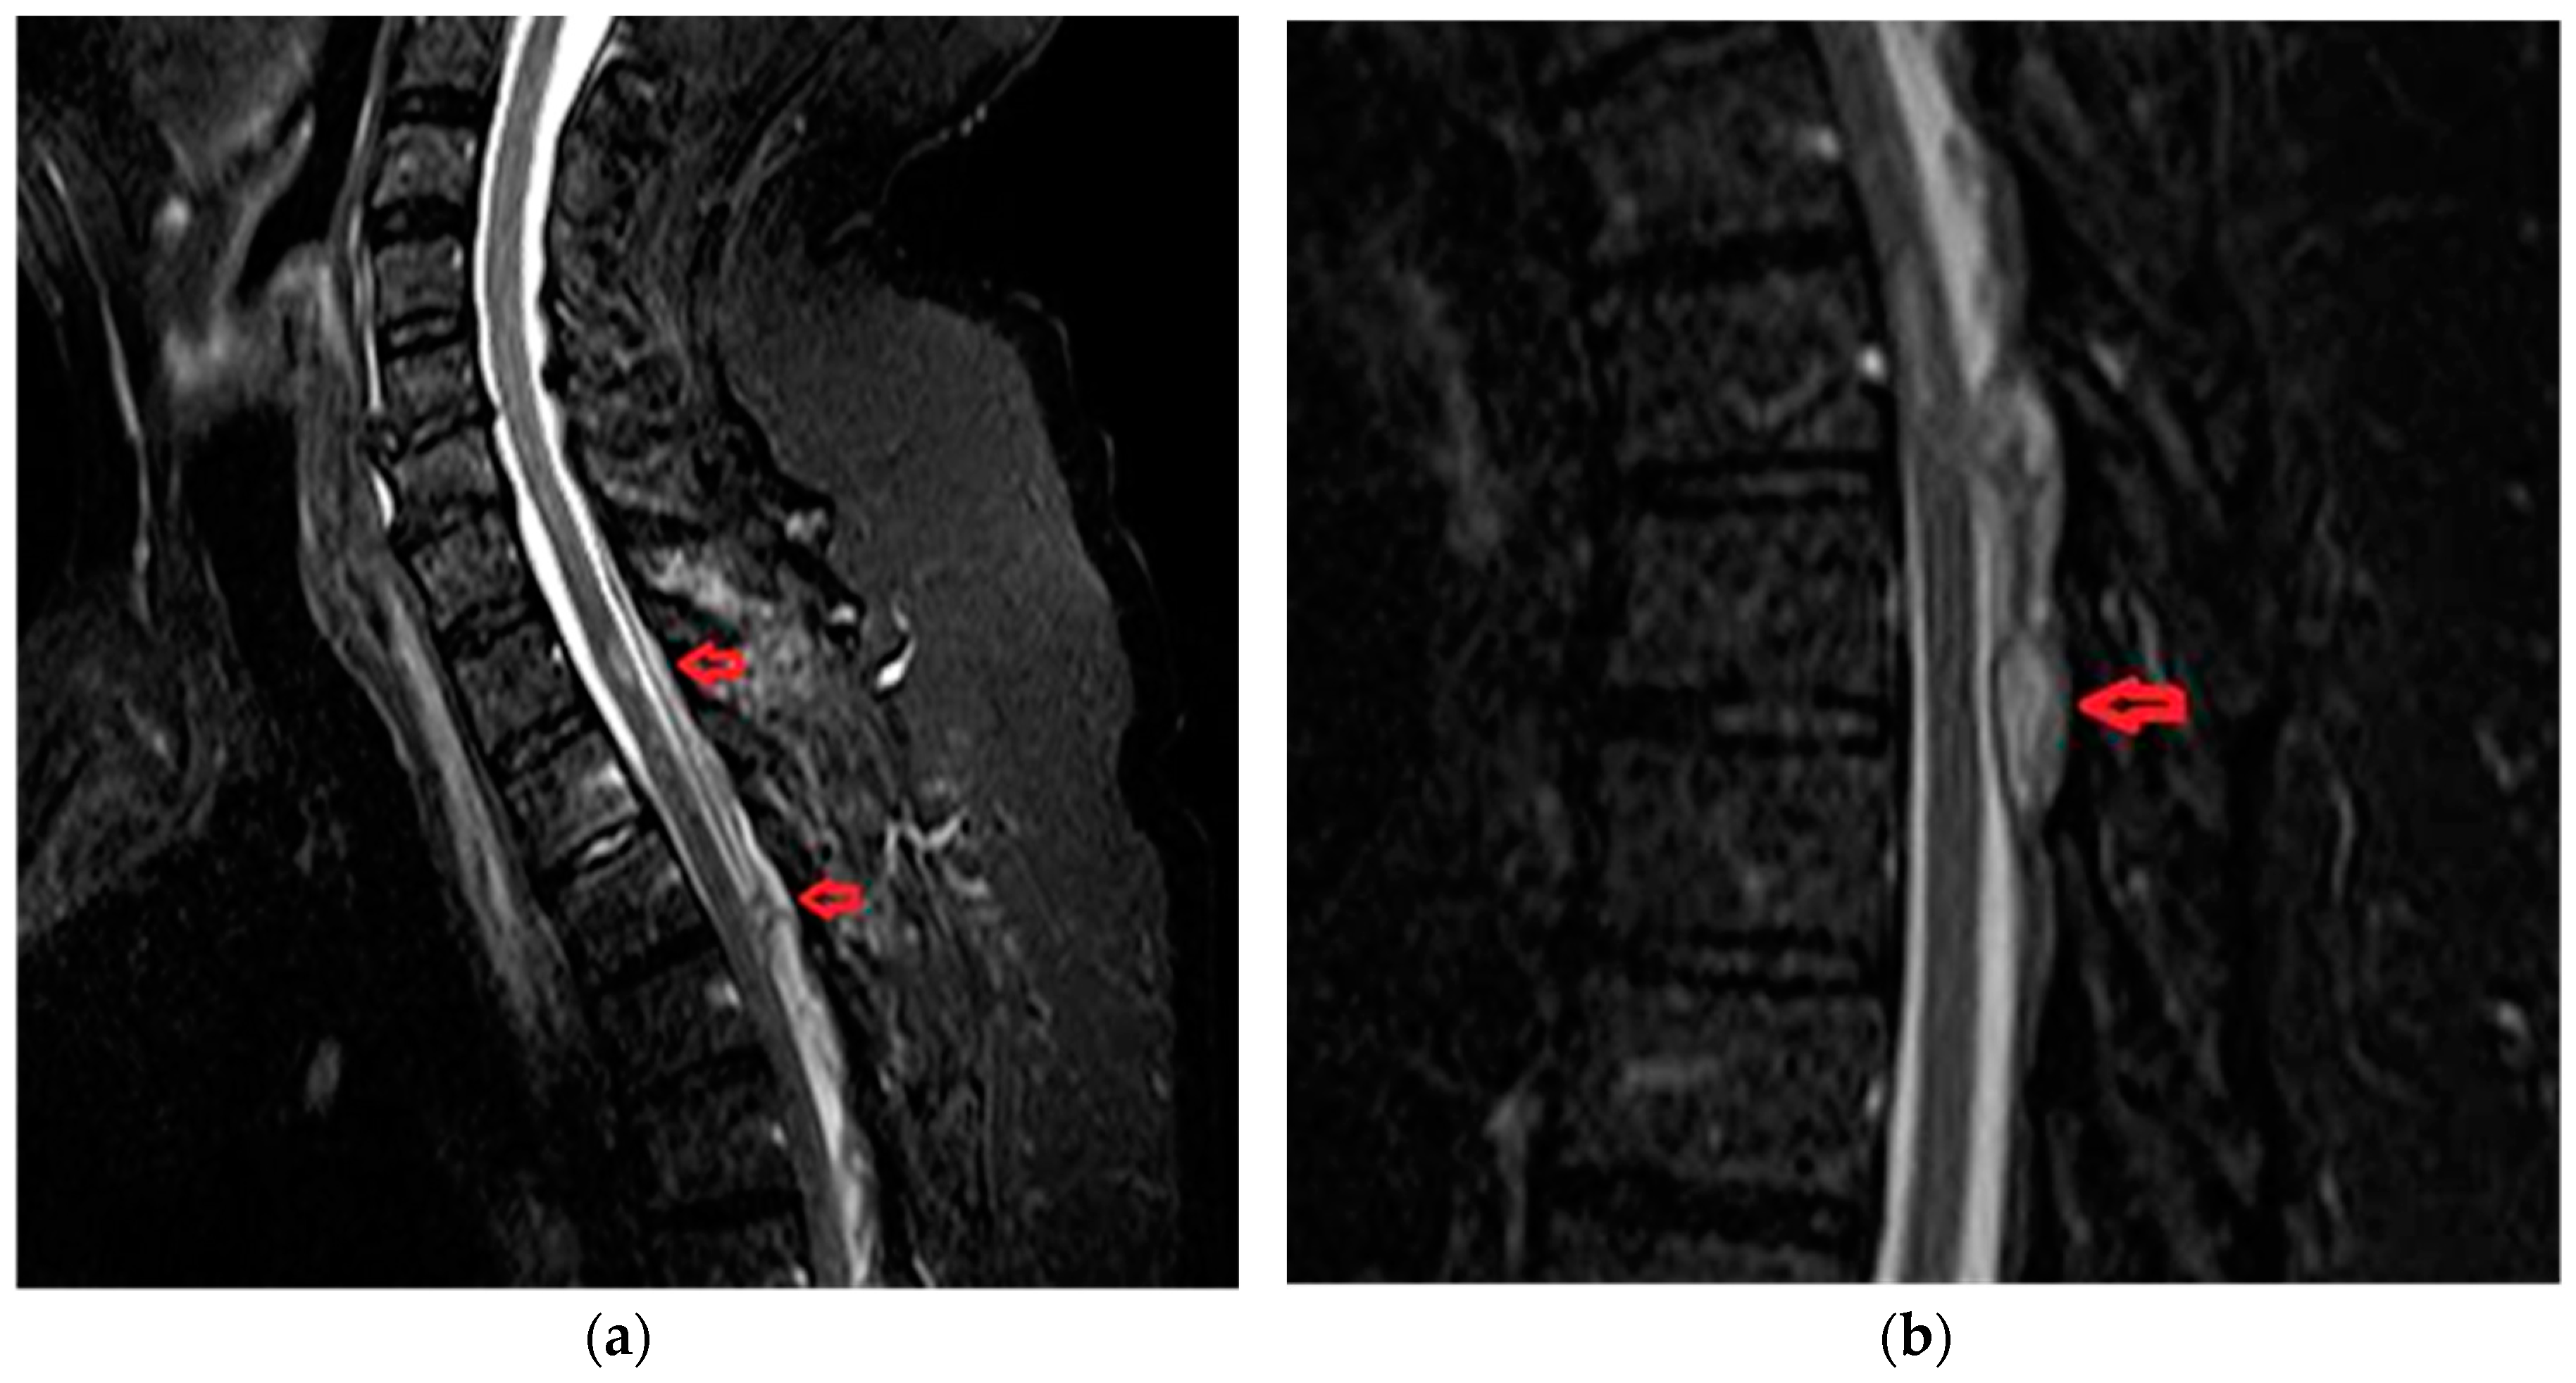

A 32-year old female, with subacute onset in three weeks, presenting with asymmetrical paraparesis, spinothalamic type sensory deficits. Posterior column sensory functions (vibration and position sense) are spared. Micturition disturbance was present. Back pain was present at onset with VAS score 6 (moderate pain). Imaging data is available in Figure 5.

Figure 5. (a) Fast-spin-echo-T2-weighted image shows hyperintense cord from T6 to T10 and serpentine flow voids, consistent with enlarged intradural vessels, posterior to the cord from T6 to T10. (b) Digital subtraction angiogram (anteroposterior view) following injection of the right T6 posterior intercostal artery demonstrates a fistula in the region of the right neural foramen with drainage into the canal via the medullary vein.